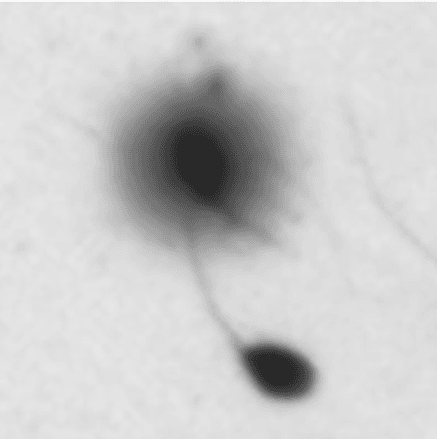

W naszym laboratorium badanie integralności chromatyny wykonywane jest metodą SCD (ang. Sperm Chromatin Dispersion). Test oparty jest na reakcji denaturacji kwasowej DNA. Podczas inkubacji ze specjalistycznymi odczynnikami w próbkach zawierających prawidłowe DNA dochodzi do rozplecenia oraz wybarwienia dwuniciowej struktury kwasu nukleinowego na skutek zerwania wiązań łączących nici DNA ze sobą, a w obrazie mikroskopowym zauważalny jest tzw. efekt halo. U plemników zawierających nieprawidłową strukturę chromatyny efekt halo jest niezauważalny bądź znikomy. Im mniejsze halo obserwujemy pod mikroskopem, tym stopień fragmentacji chromatyny jest wyższy.

1. Obraz mikroskopowy plemnika z wyraźnym halo - chromatyna niepofragmenowana.

2. Obraz mikroskopowy plemnika, brak halo – chromatyna pofragmenowana.

3. Porównanie plemników z odmienną strukturą chromatyny - plemnik górny z prawidłową chromatyną, plemnik dolny bez efektu halo - chromatyna pofragmentowana.